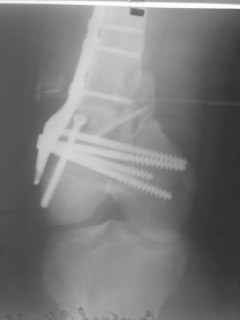

01.12.09г. оперировал больного с подобной травмой в ЦРБ на 4-е сутки

после ДТП. Перелом открытый - рана находилась медиально чуть выше

надколенника длиной примерно 3-4 см. До этого при поступлении было

выполнено ПХО раны и скелетное вытяжение. На момент операции рана без

признаков воспаления, состояние больного удовлетворительное.На

первичных снимках перелом А3. На операции оказалось С3. Перелом

фиксирован мыщелковой пластиной. Для репозиции понадобился медиальный

доступ. Медиальный блок дополнен костно-губчатым аутотрансплантатом.

На сегодняшний день раны заживают первично, швы еще не сняты,

температура тела нормальная, отек бедра значительно уменьшился,

имеется анемия средней степени, проводится ЛФК. Фото досылаю